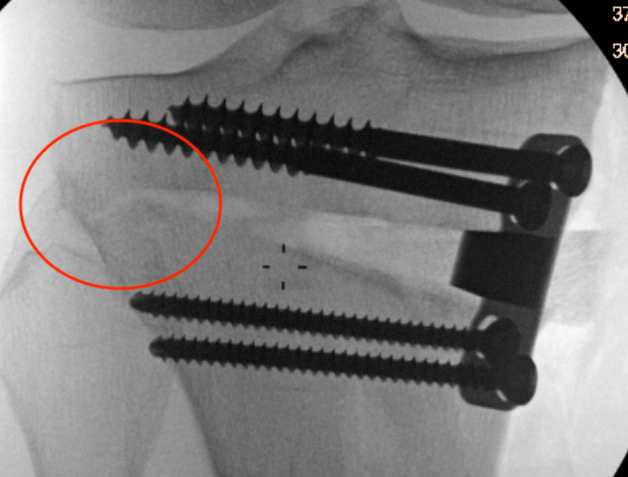

Lateral hinge fracture

Type I hinge fracture

Definition

Extension of the osteotomy into far cortex

May be associated with instability / delayed union / nonunion

Classification lateral hinge fracture after OW HTO

Takeuchi classfication

- type I: extend into lateral cortex above proximal tibio-fibular joint

- type II: extend into lateral cortex below proximal tibio-fibular joint

- type III: extend into lateral tibial plateau

Type II hinge fracture